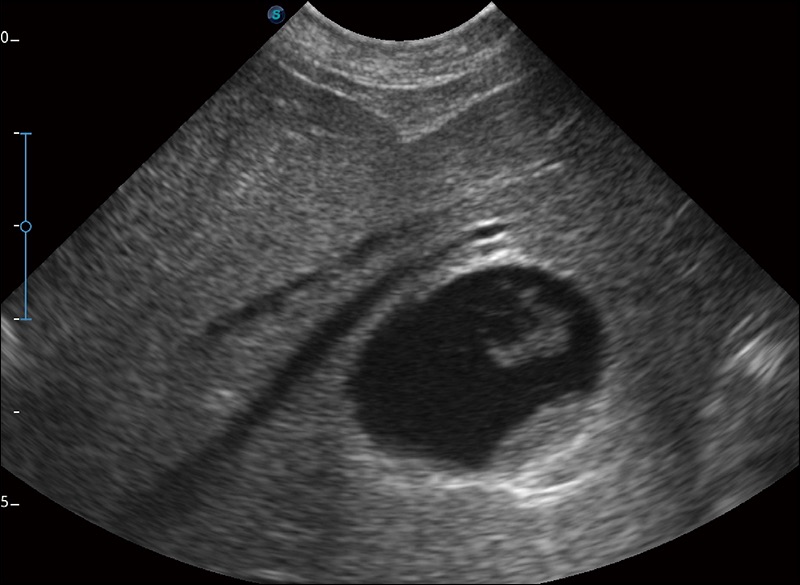

精致轻巧 性能迅捷

α1卓越的图像质量和便捷的工作流程,使每位宠物医生都能轻松扫查。其全面的兽用应用功能和紧凑型的结构设计,可以满足动物检查的多种需要。专业的预设检查模式和多领域测量软件包有助于为不同类型的动物提供检查, 让宠物医生能够出色的完成工作。